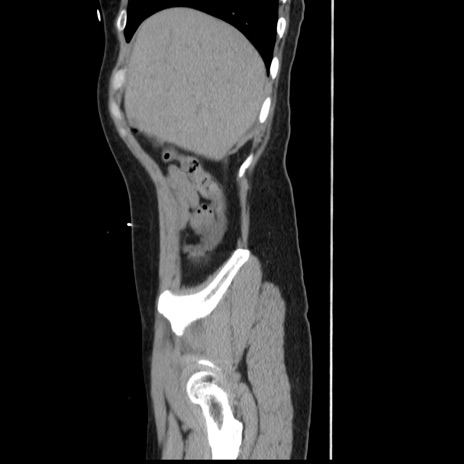

症例10(矢状断像)

【症例】 50歳代女性

【主訴】 腹痛

【現病歴】前日生レバーを食べた。今朝に排便あり。 昼前に突然発症の腹痛を生じ、当院救急外来を受診した。

【既往歴】 子宮筋腫にてで子宮全摘後

【身体所見】 意識清明、腹部:平坦、軟、下腹部やや左を中心に圧痛・反跳痛あり、筋性防御あり

【データ】WBC 7800、CRP 0.07